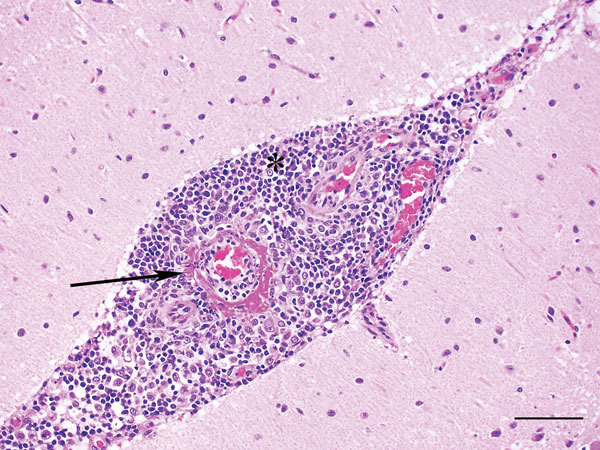

Description:Hendra virus occasionally causes severe disease in horses and humans. In Australia in 2013, infection was detected in a dog that had been in contact with an infected horse. Abnormalities and viral RNA were found in the dog's kidney, brain, lymph nodes, spleen, and liver. Dogs should be kept away from infected horses.